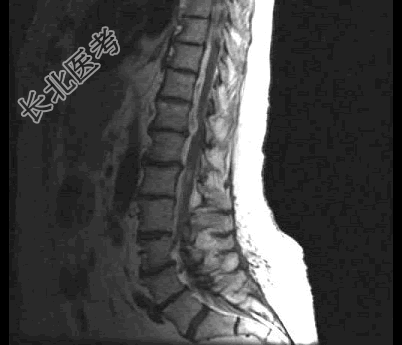

- 单项选择题患者,女, 68岁,头部剧痛伴左上肢无力半月余, 近两天发展为双下肢截瘫,请结合影像学检查, 选出最可能的诊断 ( )